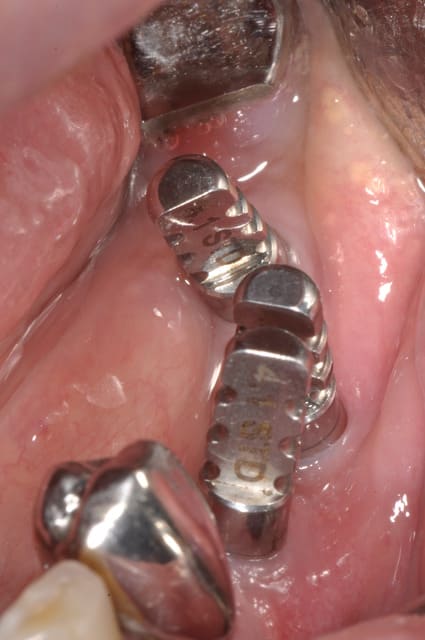

Implants posés le 31/05

juste une incision crestale au moment de la mise en place des implants, je n'arrive pas à faire tout transgingival comme le fait notre confrère Nedjat avec ses implants.

Je te mets la cicatrisation à 24h,çà me plait bien, ce sont des implants Léone